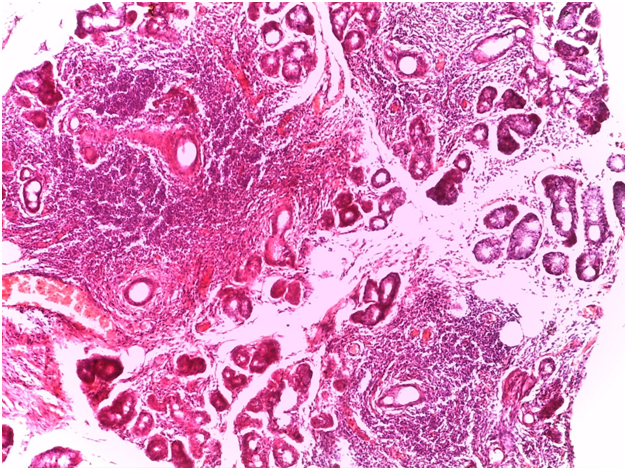

For Sjögren’s syndrome, salivary gland biopsy specimens have shown numerous lymphocytic foci in 4 mm2 (count > 50 lymphocytes per focus) within the glandular parenchyma. Acinar degeneration and few epimyoepithelial islands were detected. There was no substantial confluence of lymphocytes in a germinal-center-orientation within the submitted cases (Figure 3 & Figure 4). Focusing on characterizing any histopathological changes in GBS, the submitted cases of GBS revealed, in the asymptomatic glandular specimens, conspicuous perivascular and periductal infiltrations of neutrophils and macrophages. Moreover, vascularity was richer than that of normal mucosa whose vascular components were inconspicuous. Hemorrhagic spots, intervening extravasation of RBCs as well as dark acini, comparable to dust cells in smoking alveolitis, were also evident (Figure 5 & Figure 6).

Figure 3 Photomicrograph showing confluence of lymphocytic foci that infiltrate most of the architecture of the glandular parenchyma with acinar degeneration and epimyoepithelial proliferations. (H&E stained, Original magnification 10x).

Figure 4 A higher magnification of the previous photomicrograph in which a confluence of lymphocytes replaces the glandular parenchyma and degenerates the acini. (H&E stained, Original magnification 40x).

Gilbert-Behçet syndrome characterizes no specific findings. The general histological pattern of neutrophilic infiltrations, lymphocyte aggregations of the surrounding vessels and vascular proliferations have been observed in biopsy specimens of oral apthae and genital ulcers. However, none of these is specific. Moreover, accumulation of lymphocytes, neutrophils, and eosinophils as well as edema and leukocytoclasia occur at the site of the pathergy test within the first 12 hours.16,17 Again, this may hold true at any non-specific inflammatory site. This study appreciate the conspicuous perivascular and periductal infiltrations of neutrophils and macrophages, the rich intervening vascularity and the dusty acini in GBS. The characteristic lymphocytic within the atrophic glandular parenchyma, acinar degeneration and proliferations of epimyoepithelial islands were substantially remarkable in all labial salivary gland specimens of SS. This highlights the diagnostic validity of this biopsy in diagnosing such rheumatic diseases. Immunohistochemically, the moderate to strong expression for CD68 implied the high propensity of macrophages aggregations on the normally appearing acini; possibly attacking some bacterial strands with streptococcus sanguinis highly suspected. Similarly, the moderate to strong expression expression for CD16b indexed an affininty of perivascular and periductal neutrophilic infiltration. Staining strongly for CD34 has marked the proliferative incidence of endothelial vessels and increased intervening vascularity which signifies the vascular pathognomonicity of GBC. The negative expression for cathepsin-K emphasizes the non-granulomatous content of both GBS and SS. Reviewing the literature, caveats of exacerbating GBS encompassed, quite correctly, uveitis, aneurysms and CNS responses of which recurrent uveitis was considered highly striking for liability of visual loss, especially in the left eye.18-20 This find goes hand in hand with the present study therein uveitis was commonly observed.